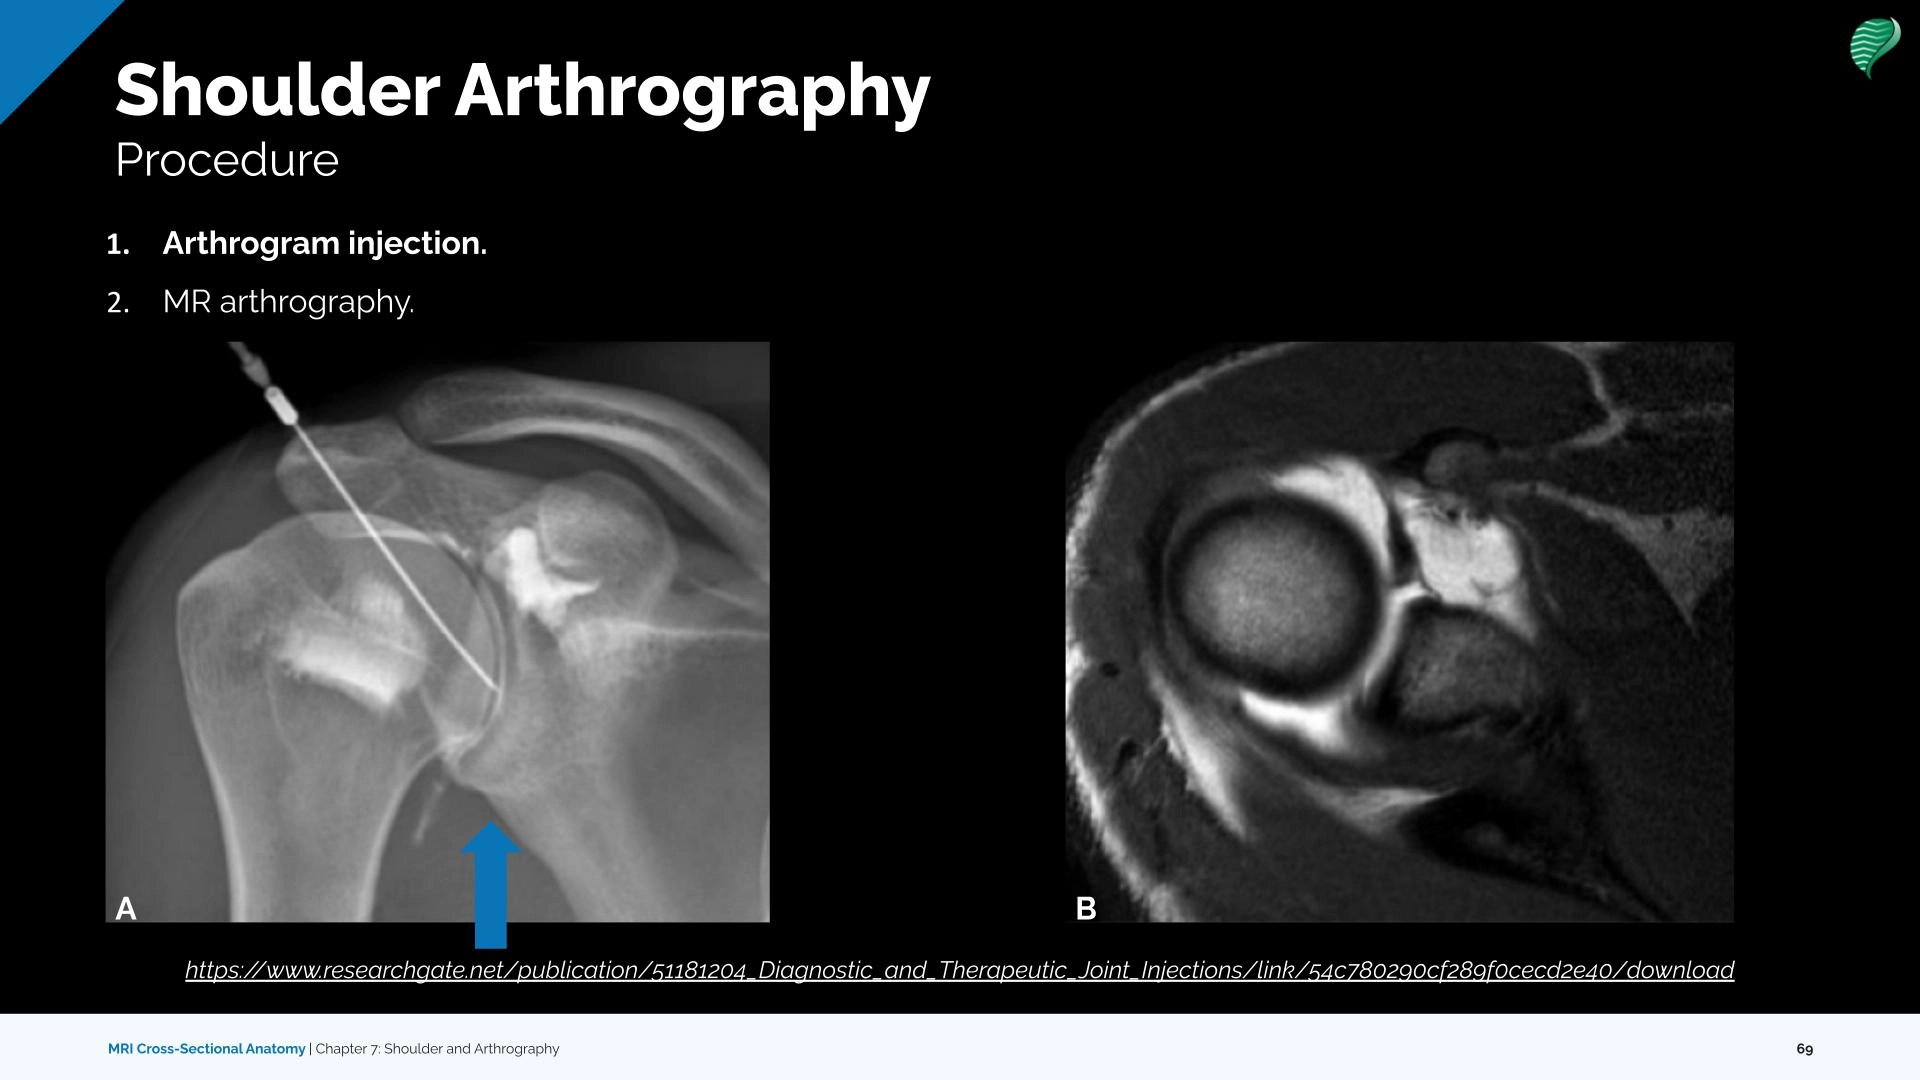

Diagnostic and Surgical Imaging Anatomy: Musculoskeletal。Morphological Parameters of the Hip Joint and Its Relation。Knee MRI (Approach to MSK MRI Series) - YouTube。原書 MRI ARTHROSCOPY and SURGICAL ANATOMY OF JOINTS David W Stoller 磁気共鳴画像法、関節鏡検査、および外科的解剖アトラス20数年前Williams & Wilkins本社から直接US$289.00で購入したものです。 下記の説明文参照してください。 このアトラスには、500 件を超える MRI スキャンと 200 件を超えるフルカラーの関節鏡検査および外科的解剖写真が掲載されており、MRI、関節鏡検査、外科解剖学の間の直接的な相関関係が示されています。 各章は、関節鏡検査と外科解剖学に関する著名な整形外科医による解説から始まります。CD-ROM - 1999年1月15日by デビッド・W・ストーラー (著者) この見事なマルチメディアCD-ROMには、ストーラー博士の鮮やかなイラスト入りMRI、関節鏡検査、関節の外科解剖学の本の全文とすべてのイラストに加えて、関節鏡のデモンストレーションと死体解剖の約30分のビデオが含まれています。ユーザーは、290枚の4色の解剖線画、関節鏡写真、外科解剖写真を含む800以上の画像にワンクリックでアクセスできます。】。CT & MRI Cross-sectional Anatomy Package | 30.75 CE credits。 MRI 関節鏡検査機器及び詳細な外科的治療解剖解説図が三次元的に取り入れられて大変解りやすく紹介されている 整形外科を学ぶ上で必須な専門書です。専門医取得に必要な形成外科手技 37 上下セット。【新品未使用】ACLSプロバイダーマニュアル AHAガイドライン2020準拠。 【このアトラスには、磁気共鳴画像法、関節鏡検査、および外科的解剖で見られる肩、足首、股関節、膝、手首、肘の解剖学的構造が生き生きと描かれています。【新品・未使用】ぎゅっとアウトプット本 全18冊セット 最終値下げ!。生体律動調整法 茂木 昭 著。 死体の関節の MRI スキャンは、同じ死体標本の関節鏡および外科的解剖写真と並べて表示されます。NCプログラム 全3巻セット。ヒューマンボディ版英語版 未開封品。 MRI、関節鏡検査、および関節の外科的解剖学は、付属のCD-ROM でも解説されています。DVD トム・マイヤーズ ANATOMY TRAINS セミナー2010。陸上競技 駅伝・長距離 Drill Series。さらに、このCD-ROMには、筋骨格系MRIの多くの重要なトピックに関する第一線の専門家によるナレーション付きチュートリアルが含まれています。ワールドレップサービス アースボール グリーン。【裁断済み】バイオデザイン 第2版。ユーザーは、章、キーワード、またはトピックで検索し、すべての画像をズームアップして詳細に表示できます。ワールドレップサービス アースボール ブルー